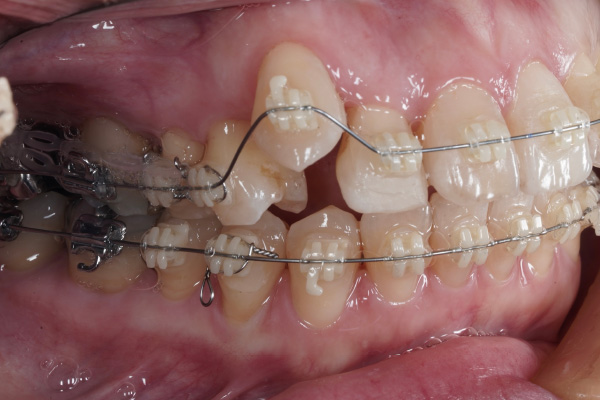

⚫︎主訴:八重歯を治療したい。前歯が咬んでないのを治療したい。

⚫︎前歯が咬んでいない

この症例の場合も、4ヶ月→8ヶ月で目に見える変化がありました。